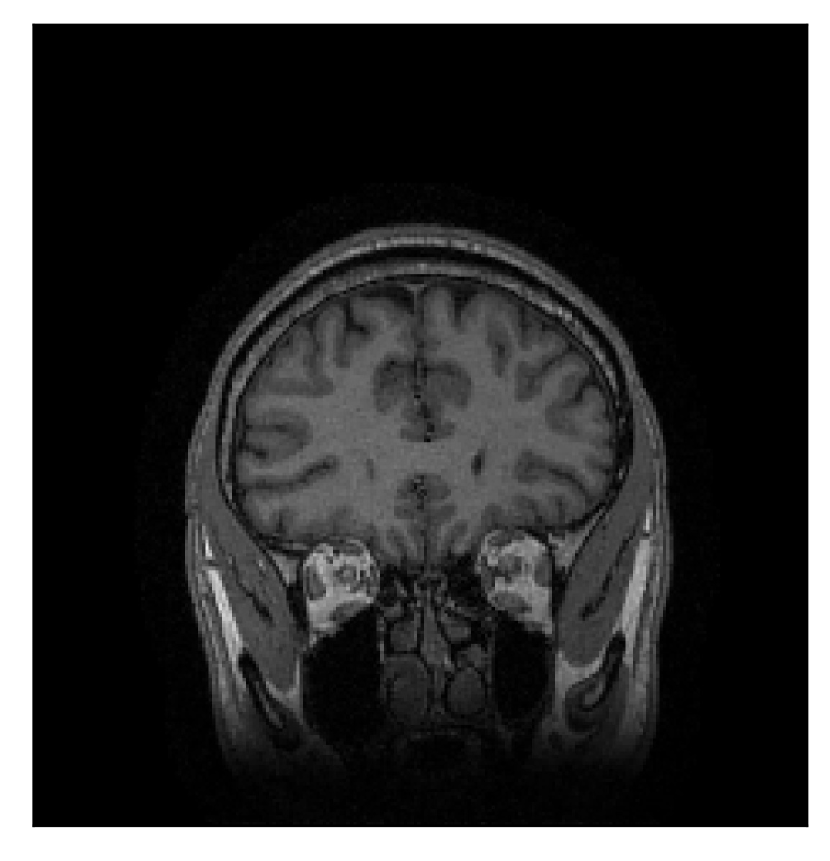

We consider three levels of motion corruption: (i) the volunteer moves once, (ii) the volunteer moves twice, and (iii) the volunteer moves five times. The volunteer is instructed to change its head position every time it is prompted to do so, and maintain that position in between instructions. We use T2-FLAIR-weighted contrasts as corrupted scans, with T1-weighted contrast as a reference (see Table 1 for further details). The corrupted acquisition employs randomized sampling.

| Section 3.1, Figure 2 | Sagittal | 23.94 | 27.95 | 0.7068 | 0.7936 |

| Coronal | 26.66 | 29.82 | 0.7653 | 0.8332 | |

| Axial | 25.40 | 30.16 | 0.7616 | 0.8490 | |

The motion-corrected full-volume scans were analyzed by a neuroradiologist with 16 years of experience. These were generally deemed of good radiological quality. The motion-related artifacts have been completely removed, and the results are quite close to the ground truth. In Table 3, we organized a more detailed qualitative analysis of the 3D results, geared toward a radiological assessment of the corrected scans.

| Section 3.1, Figure 2 | T2-FLAIR | Completely corrected | Some blurring | No additional artifacts | Good grey white matter differentiation |

4.1 Experiment 1: robustness test

We gather the results for the robustness test described in Section 3.1 (volunteer 1) in Figures 2, 4, and 6 for motion corruption mechanisms associated to one, two, and five changes of position, respectively. Furthermore, we juxtapose the corrected images with varying degrees of corruption in Figure 8. We observe that the proposed method consistently ameliorates the corrupted scan. The quality indexes based on PSNR and SSIM show only a modest decrease in correction quality as a function of motion complexity (Figure 8).

Our experimentation based on volunteer data aimed at assessing the robustness of the correction quality with respect to motion artifacts of increasing complexity. In this study, we equated this complexity to the number of volunteer changes of pose during the acquisition phase. Clearly, this does not fully describe the complexity of motion encountered in practice in the clinic, but it only constitutes a preliminary step in that direction. Nevertheless, the results described in Section 4.1 support the indication that the retrospective motion correction of T2-FLAIR weighted images based on a T1 reference contrast is quite robust in terms of reconstruction quality, with only minor degradations in terms of contrast and resolution.

Sagittal

Coronal

Axial

Axial detail